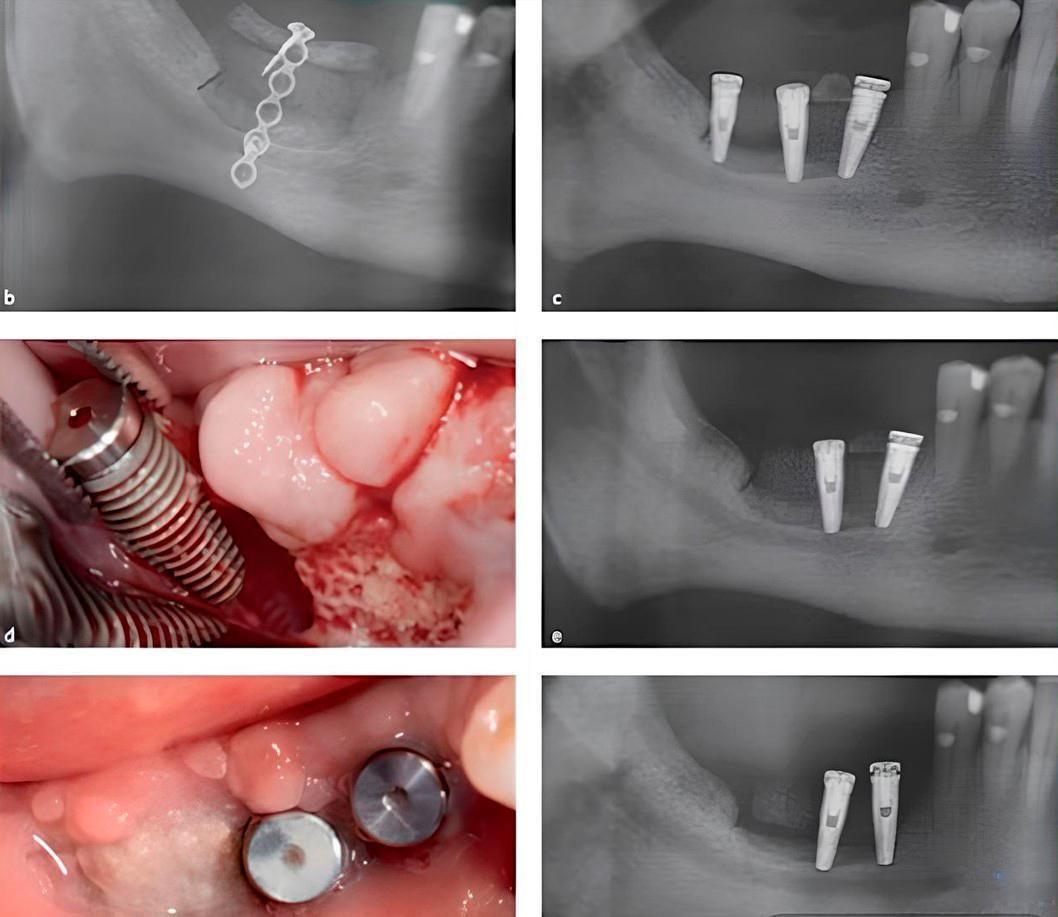

As an example, we will look at a case by Dr. Marco Esposito, published in the following article:

The issue arose after a failed attempt to increase alveolar ridge height. The situation was ultimately resolved using short implants. Initially, the technique used was augmentation with xenogeneic bone blocks.

While this technique can yield good results, in this specific case, the block was completely rejected and lost, along with the implants. Consequently, the defect became even more pronounced than it was prior to surgery.

Without going into the specifics of why the complication arose, Dr. Esposito’s team was left with a patient who had agreed to a risky surgery that failed, requiring a solution. As a temporary solution, they proposed placing short implants to rehabilitate the patient.

Placement of two short implants in the remaining bone after rejection of the bone block. YouTube/ Implantarium/ Rauf Aliyev

After the osseointegration period, Dr. Esposito’s team found that the implants were supporting the load perfectly, and the restoration was fully functional. This raises the question: why undergo risky surgery if short implants could have been placed initially?

It remains to be seen whether the use of short implants is justified and how reliable they are in the long term. However, the conclusions from Dr. Esposito’s article are clear:

Short-term data (1 year after loading) indicate that 6 mm-long implants with a conventional diameter of 4 mm achieved similar if not better results than longer implants placed in augmented bone. Short implants might be a preferable choice to bone augmentation, especially in posterior mandibles since the treatment is faster, cheaper and associated with less morbidity.”